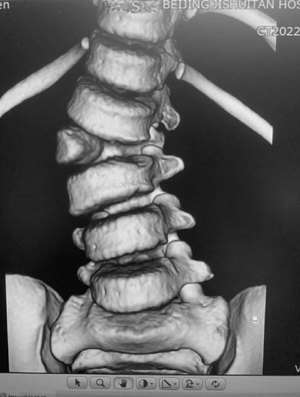

而对于何达主任医师带领的医疗团队来讲,面临着相同的挑战。孩子的年龄较小,增加了这次手术的难度,所有手术相关用物全部需要按照四岁孩子的标准进行匹配。术中,何达主任医师与韩晓光主治医师心理压力倍增,小心翼翼、准确无误的进行着每一步,最终两位医师配合默契,成功完成了手术。

手术中